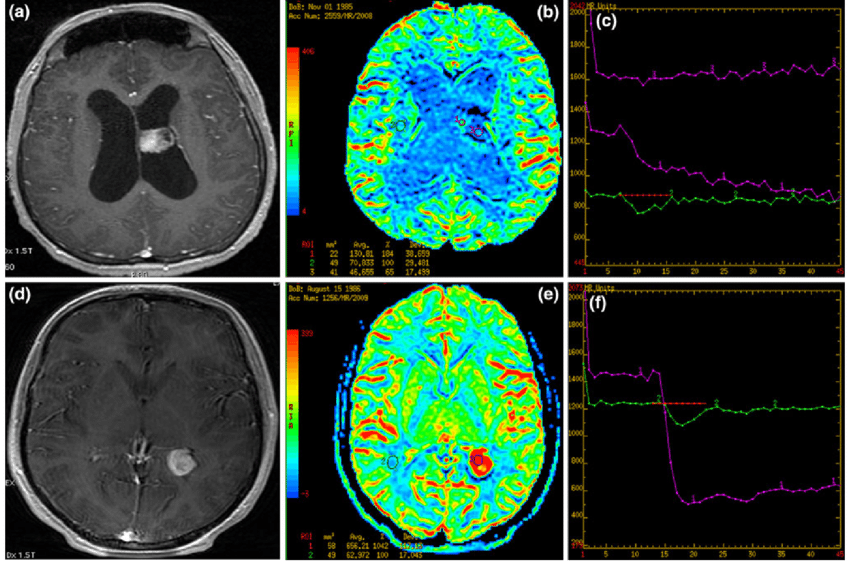

脑室肿瘤的诊断

影像学检查是脑室肿瘤诊断的关键。目前,磁共振成像(MRI)是较合适的成像方式。计算机断层扫描(CT)也被使用,特别是用于评估脑积水。在这两项研究中,都会通过静脉注射一种能提供图像对比度的药物,以便神经外科医生能在背景中看到肿瘤与正常大脑的对比。在某些情况下,神经外科医生可能使用无框架立体定向指导的MRI扫描。在这项研究中,在患者的头皮上放置不同标记(称为基准)后进行对比MRI。这些基准数据由计算机处理,计算机计算出肿瘤的位置并创建一个三维重建。这幅图像在手术时被用来帮助精确定位肿瘤,较大限度地切除肿瘤,减少对周围大脑的损伤。